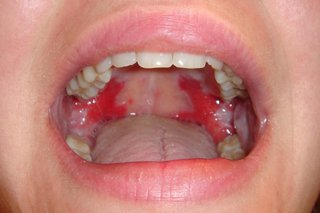

abnormalities of the oral mucosa - changes in colour - red , examples 5

(severity of) Periodontitis – Diabetes, Cardiovascular disease

Mucous membrane pemphigoid – Autoimmune

Pemphigus Vulgaris – Autoimmune

Median Rhomboid Glossitis – Candida

Erythroplakia - Smoking

Median Rhomboid Glossitis – Candida - smoker or dry mouth

Erythroplakia (red patch) - Smoking but could be a pre cancer/cancer